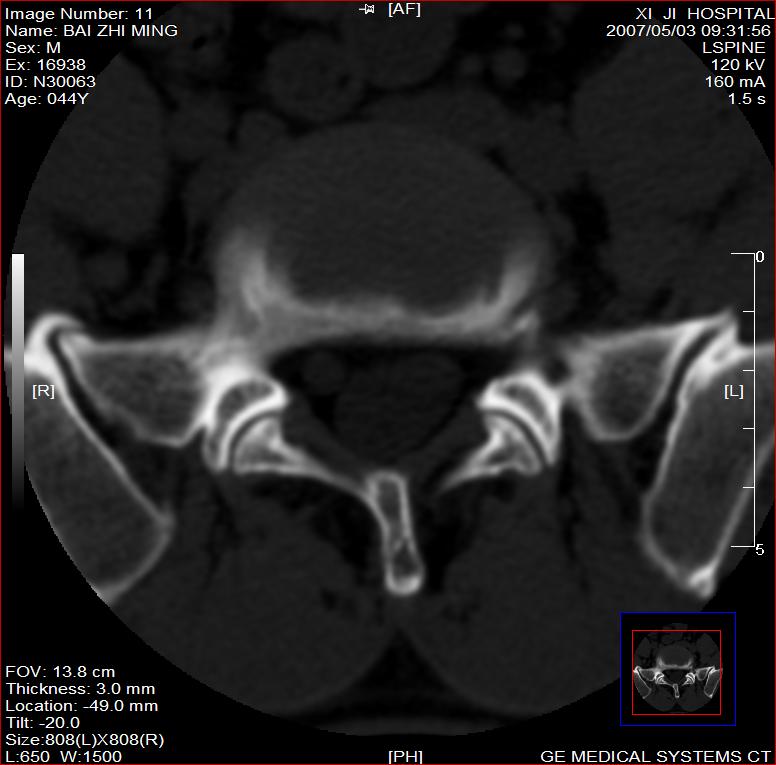

标题: CT8228:男,44岁,腰痛3月,加重3天,这是正常的吗?

男,44岁,腰痛3月,加重3天。

同意2楼,左侧神经根增粗,欠规整,神经根炎或神经源性肿瘤可能,建议mri检查。

左侧神经根增大.并硬脊膜囊受压(1,神经根炎2神经根肿瘤)

左侧神经根增粗,欠规整,神经根炎或神经源性肿瘤可能,建议mri检查